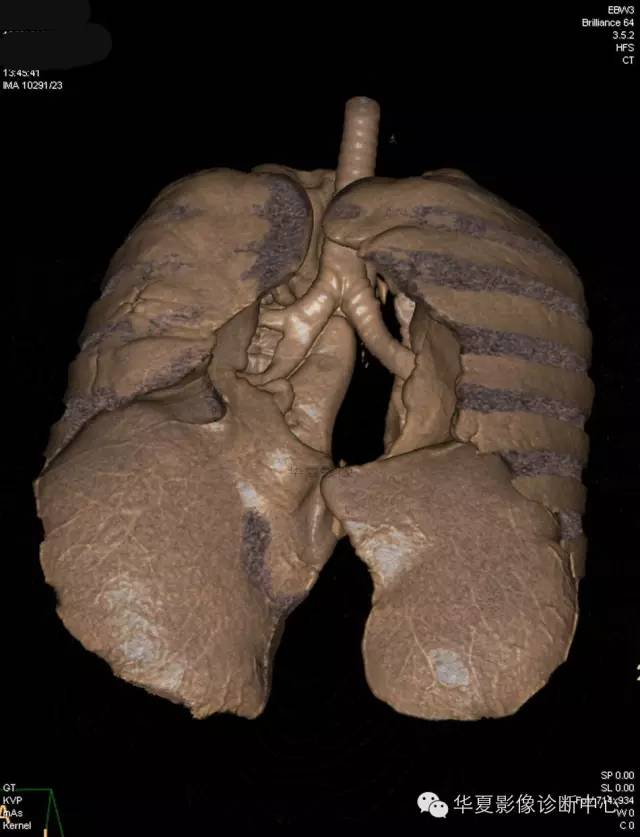

【病例学习】典型周围型肺癌CT病例一例

女,56岁,其父因肺癌去世,自觉胸部疼痛不适来诊要求拍胸片。

1.右肺上叶:肺组织1块,大小13×4×7cm。切面棕红色。2.右肺上叶肿物:灰白色组织一块,大小3×1×1.5cm。切面灰白色。3.右肺中叶结节:灰白色绿豆大组织1块。4.淋巴结:灰黑色绿豆大组织1块。

(右)肺中分化鳞状细胞癌。浸及胸膜。支气管残端切净。淋巴结未见癌转移(0/10)。